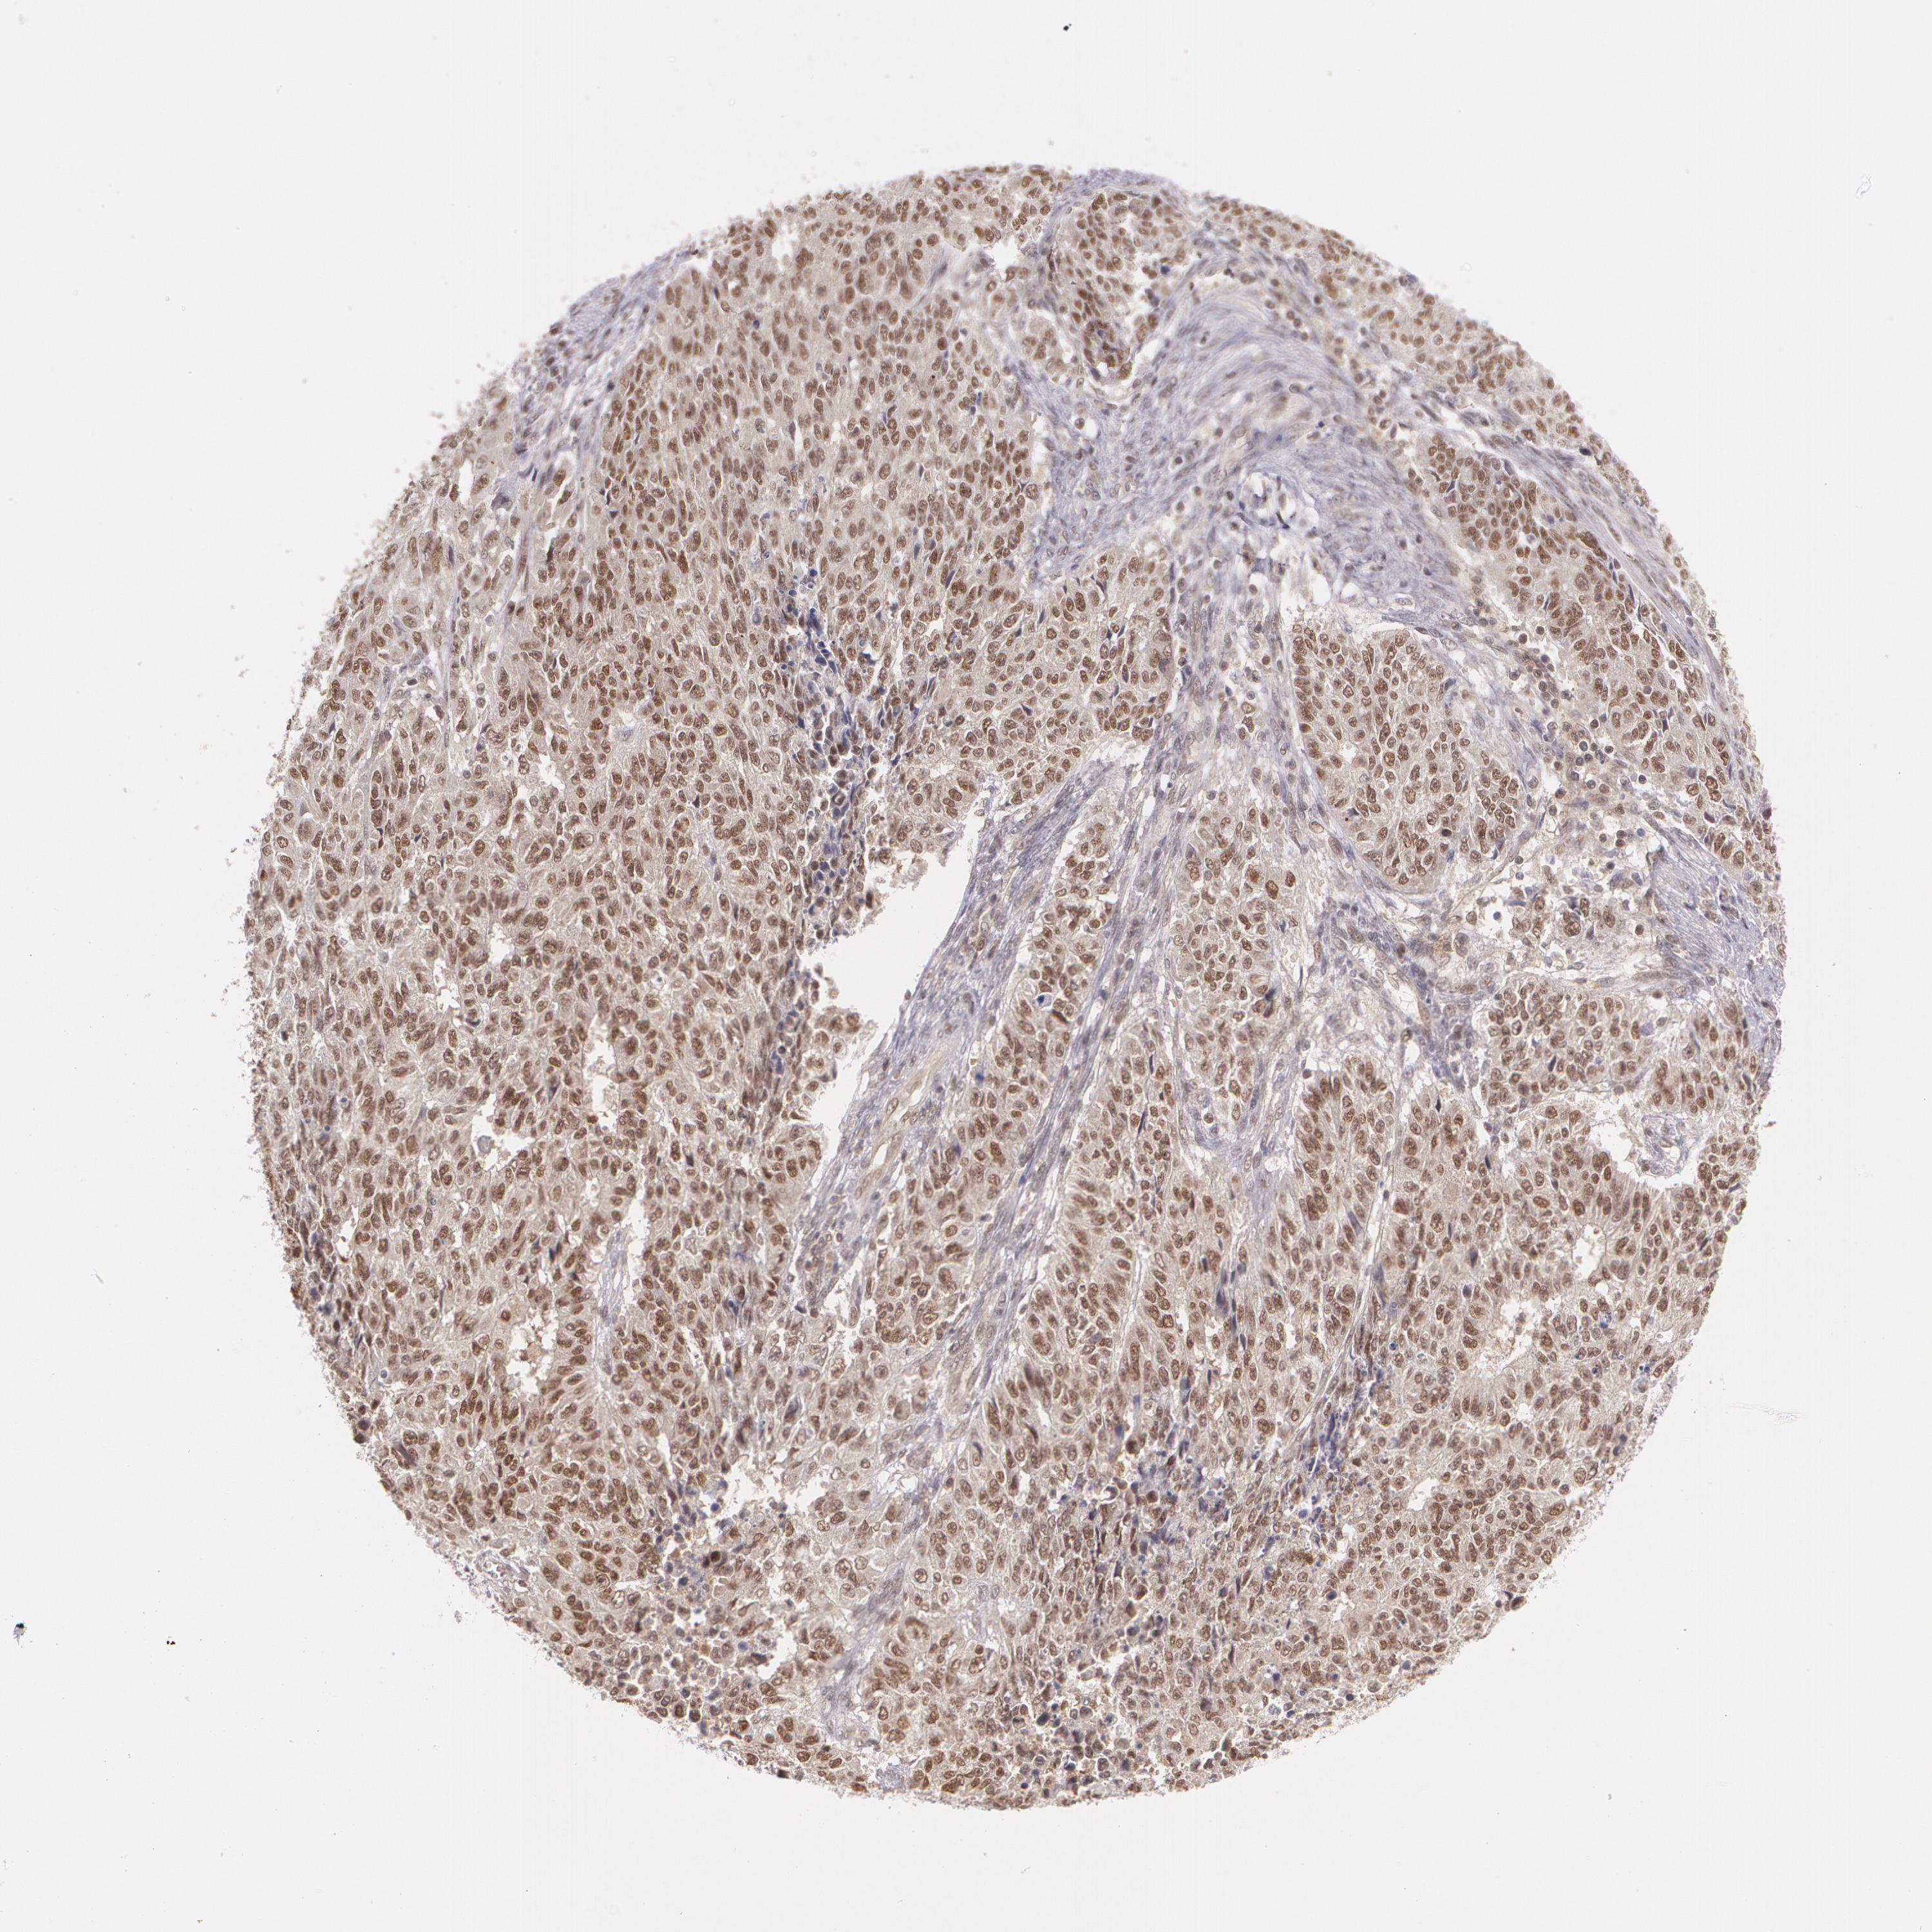

ENDOMETRIAL CANCER - Protein expressioni

A mouse-over function shows sample information and annotation data. Click on an image to view it in a full screen mode. Samples can be filtered based on level of antibody staining by selecting one or several of the following categories: high, medium, low and not detected. The assay and annotation is described here.

Note that samples used for immunohistochemistry by the Human Protein Atlas do not correspond to samples in the TCGA dataset.

Antibody stainingi

Antibody staining in the annotated cell types in the current human tissue is reported as not detected, low, medium, or high, based on conventional immunohistochemistry profiling in selected tissues. This score is based on the combination of the staining intensity and fraction of stained cells.

Each image is clickable and will lead to virtual microscopy that enables deeper exploration of all samples and also displays staining intensity scores, fraction scores and subcellular localization as well as patient and tissue information for each sample.

Antibody HPA024578

Antibody CAB002677

Staining

High

Medium

Low

Not detected

Intensity

Strong

Moderate

Weak

Negative

Quantity

>75%

75%-25%

<25%

None

Location

Nuclear

Cytoplasmic/membranous

Cytoplasmic/membranous,nuclear

Adenocarcinoma, NOS

Adenocarcinoma, metastatic, NOS

Neoplasm, malignant, NOS